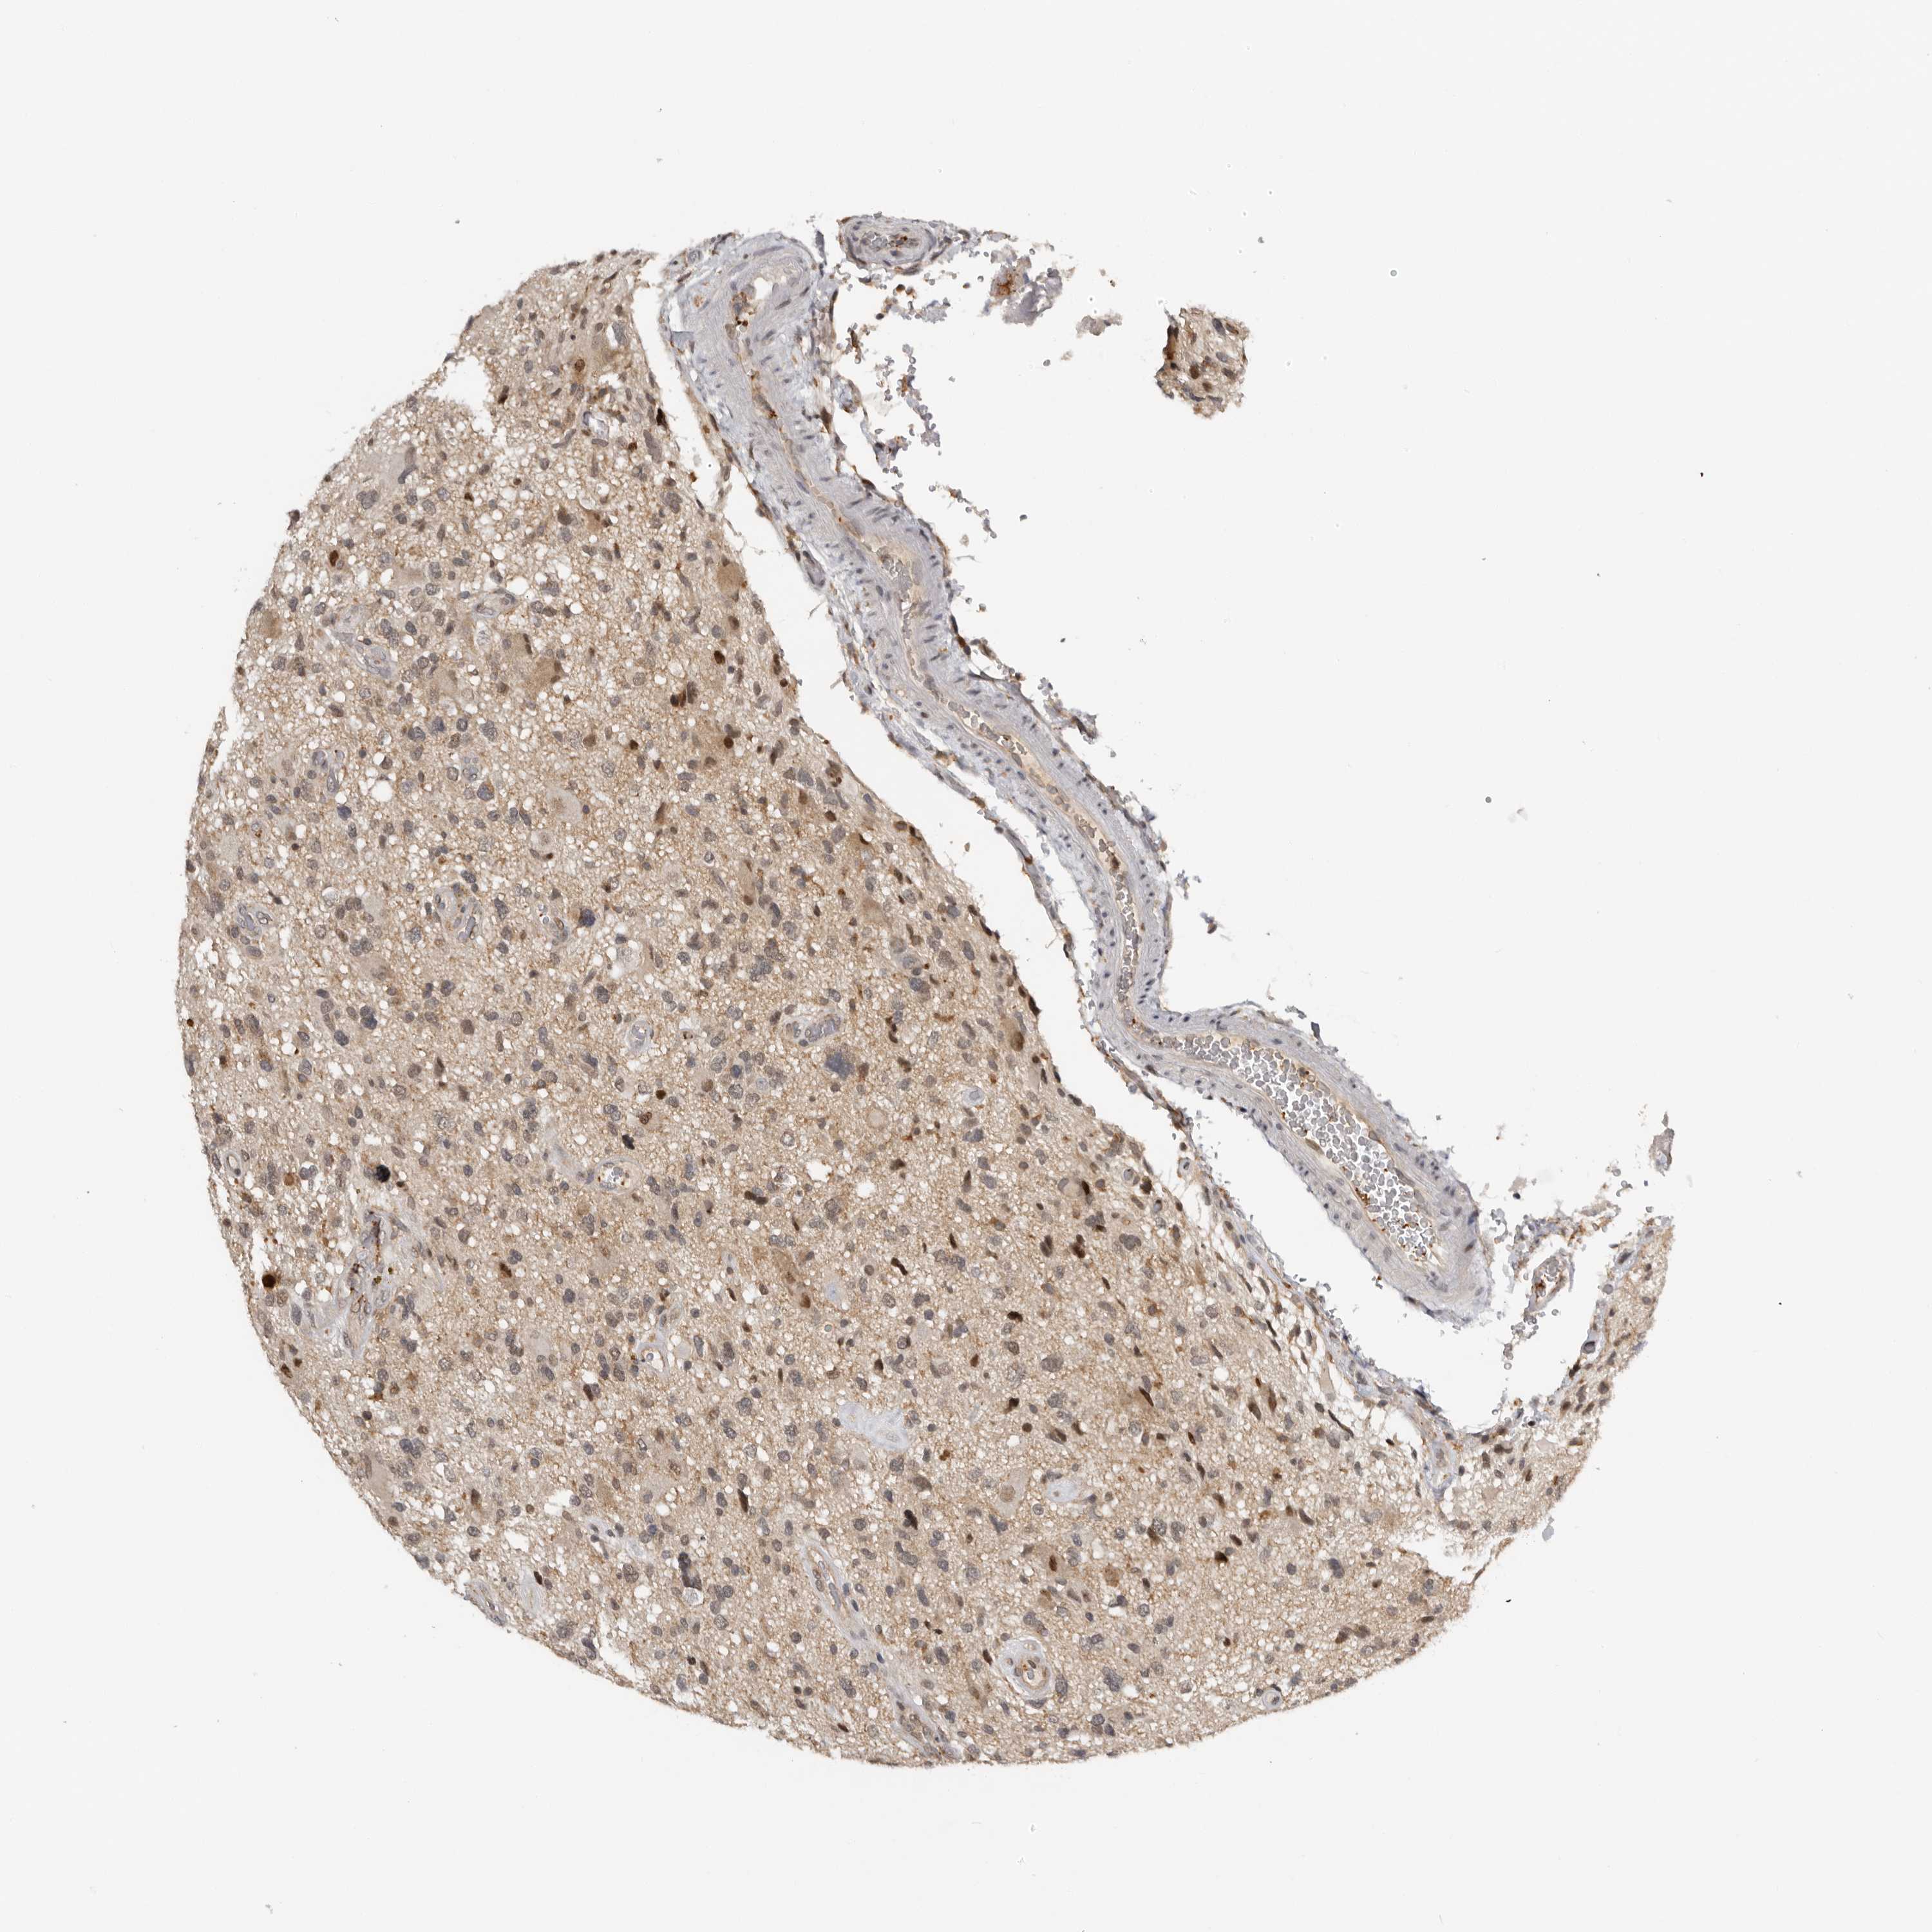

GLIOMA - Protein expressioni

A mouse-over function shows sample information and annotation data. Click on an image to view it in a full screen mode. Samples can be filtered based on level of antibody staining by selecting one or several of the following categories: high, medium, low and not detected. The assay and annotation is described here.

Note that samples used for immunohistochemistry by the Human Protein Atlas do not correspond to samples in the TCGA dataset.

Antibody stainingi

Antibody staining in the annotated cell types in the current human tissue is reported as not detected, low, medium, or high, based on conventional immunohistochemistry profiling in selected tissues. This score is based on the combination of the staining intensity and fraction of stained cells.

Each image is clickable and will lead to virtual microscopy that enables deeper exploration of all samples and also displays staining intensity scores, fraction scores and subcellular localization as well as patient and tissue information for each sample.

Antibody HPA023081

Antibody HPA023103

Antibody HPA024795

Glioma, malignant, High grade

Glioma, malignant, Low grade